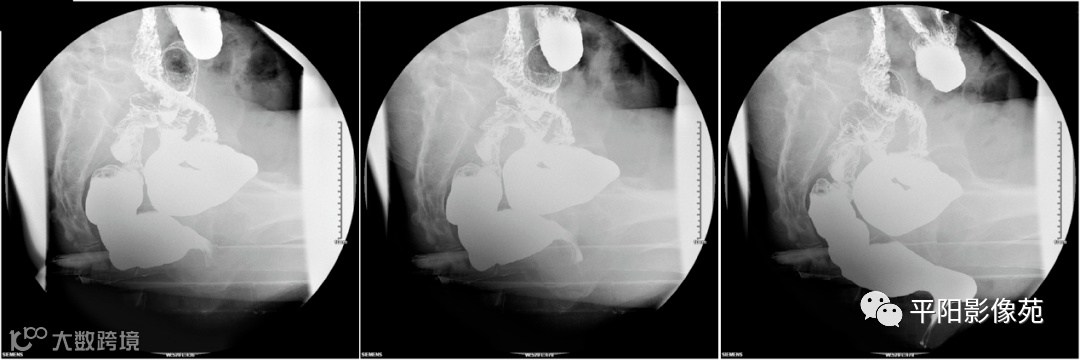

内脏下垂(splanchnoptosis,SP):指盆腔内脏器如小肠、乙状结肠、子宫等的下缘下垂至耻尾线以下者。见于力排时,乙耻距、乙(小)肛距均为正值。(图9)

图9 乙状结肠下缘位于耻尾线以下

盆底疝(pelvic floor hernia,PFH):疝内容物多为乙状结肠和小肠,可伴有附件和大网膜。依疝内容物不同分为小肠疝(enterocele,EC)和乙状结肠疝(sigmoidocele,SC)。力排时小肠或乙状结肠疝入直肠子宫陷凹或直肠膀胱陷凹内即为EC或SC。Jorge根据疝囊内乙状结肠襻的最低点,把SC分为三度:Ⅰ度位于耻尾线以上,Ⅱ度位于耻尾线和坐尾线之间,Ⅲ度位于坐尾线以下。(图11、图12)

图11 乙耻距约50mm,局部直肠受压

图12 小耻距约65mm,局部直肠受压